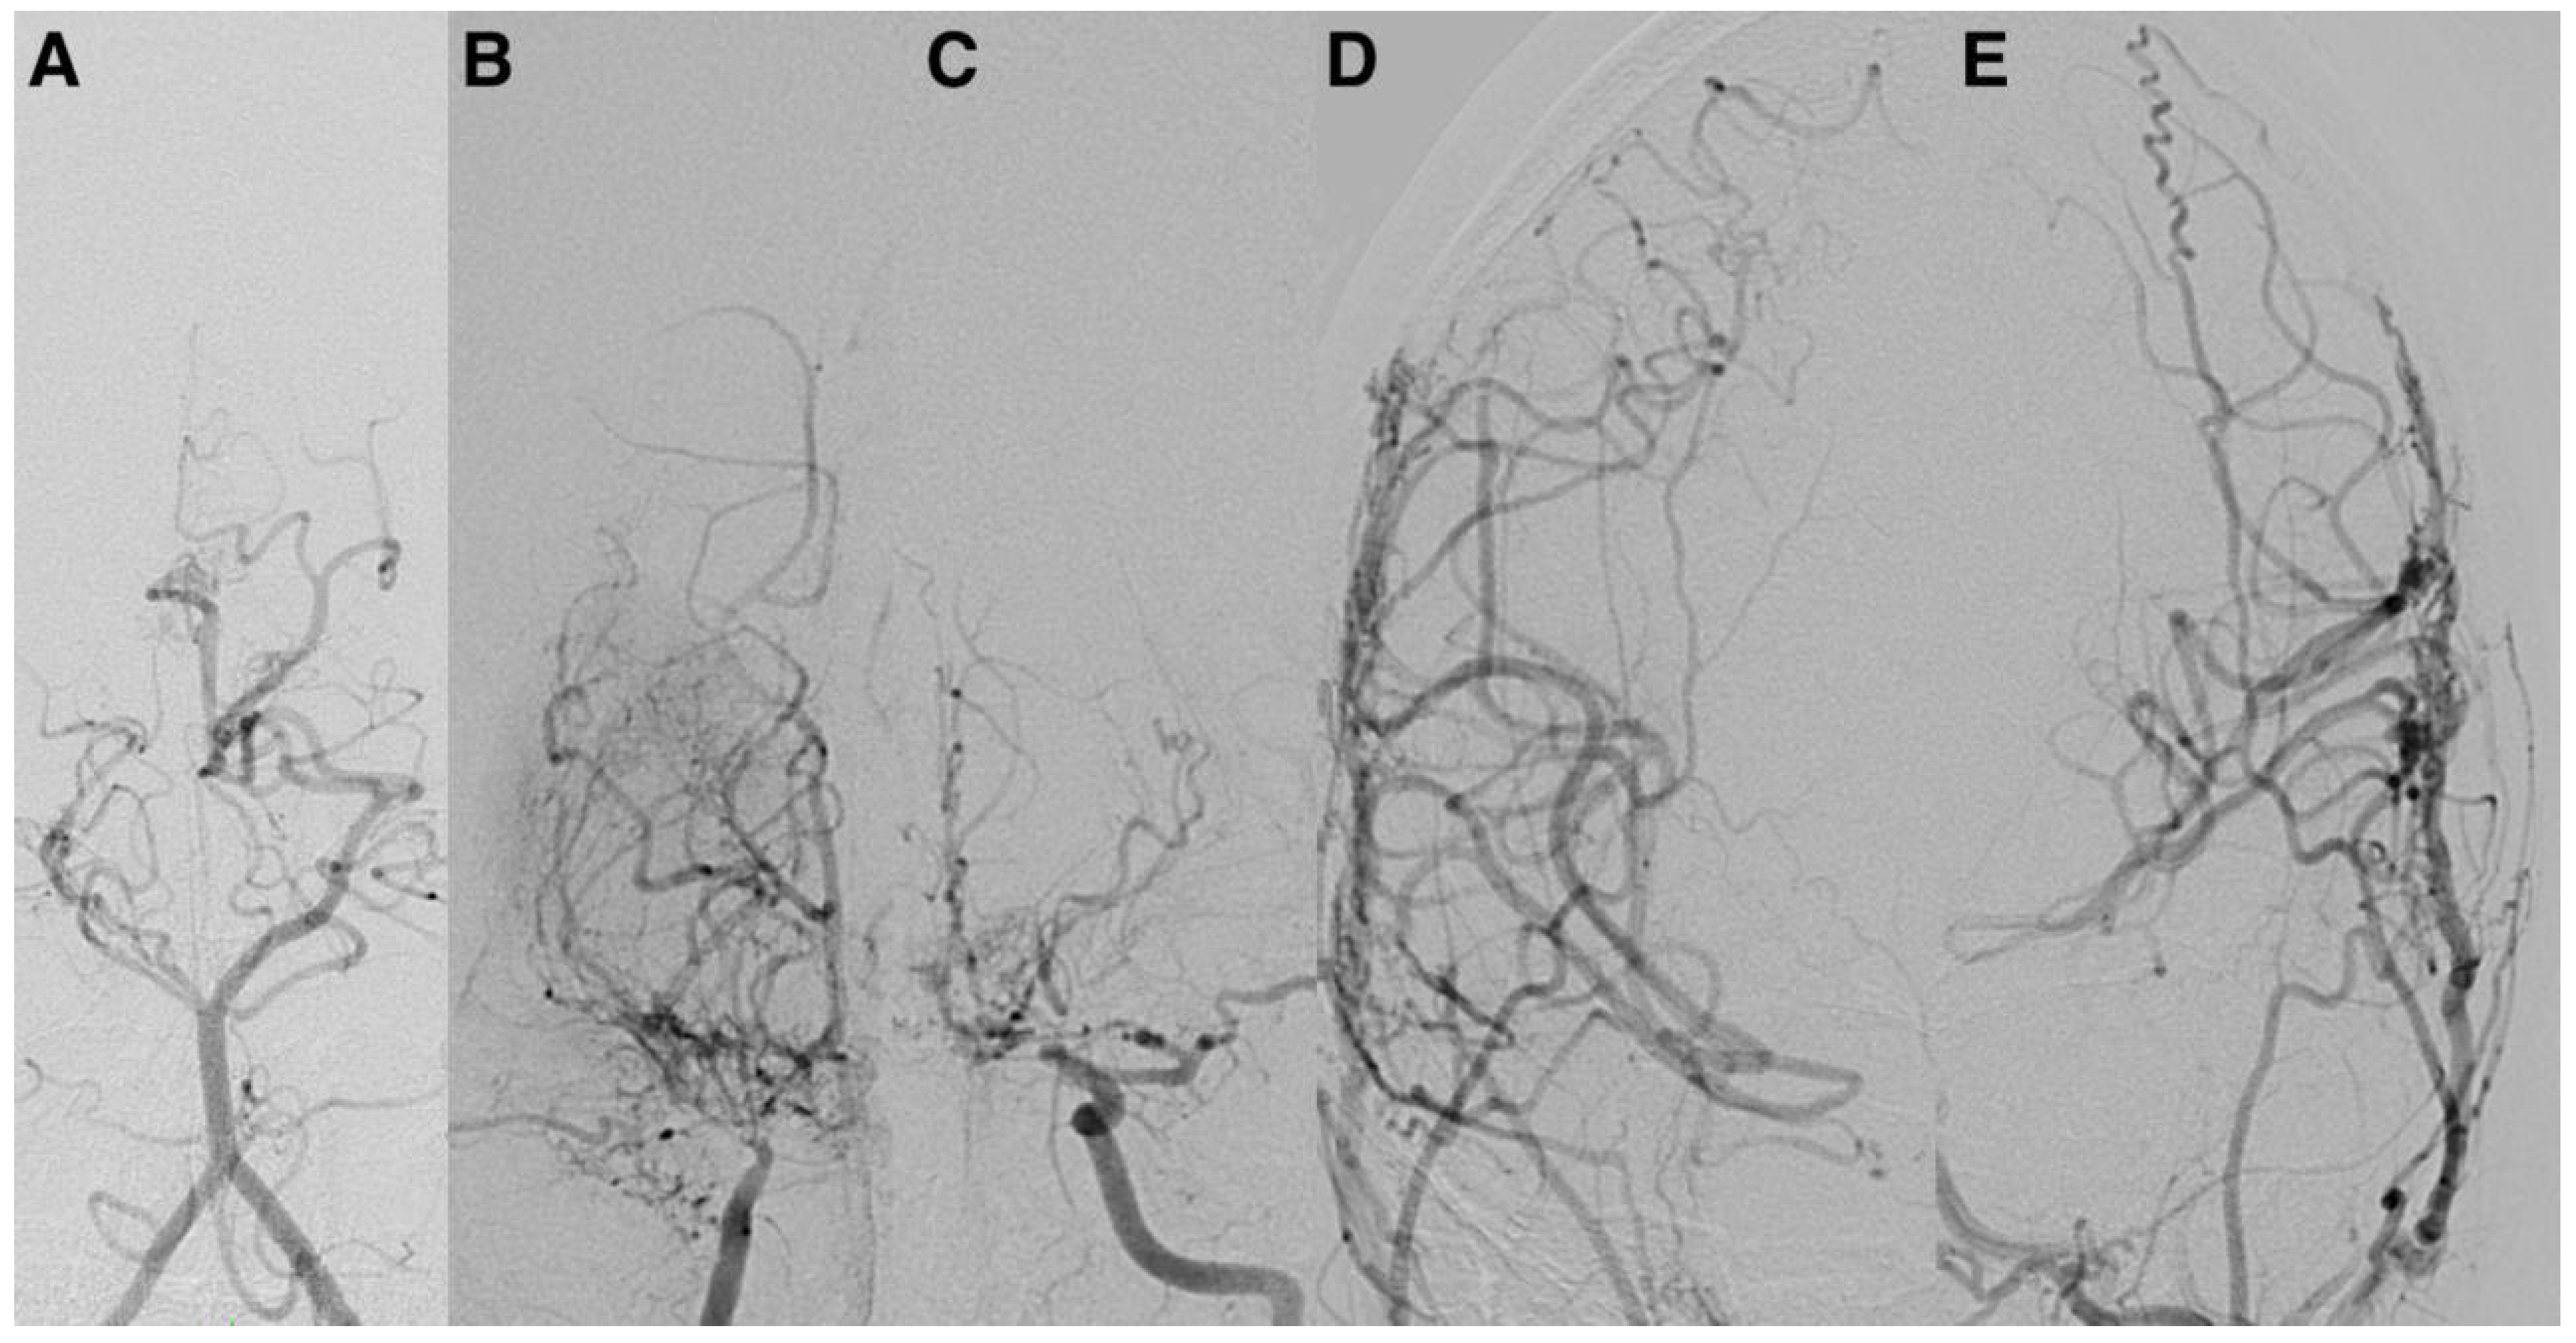

Representative postoperative angiographic images are shown in

Figure 1,

Figure 2 and

Figure 3. The mean operative time was 3.2 h and the average length of hospital stay was 7 days. All patients were monitored in the pediatric intensive care unit for 24–48 h before being transferred to the ward.

Postoperative angiographic follow-up was available for all revascularized hemispheres (n = 14) and was typically performed 3–6 months after surgery, with repeat studies conducted at 12–18 months in selected cases. According to the Matsushima grading system, six hemispheres (43%) achieved grade A and eight achieved (57%) grade B collateralization; no instances of grade C were observed.

Postoperative angiographic follow-up was available for all revascularized hemispheres (n = 14). Examinations were typically performed at 3–6 months after surgery and repeated at 12–18 months in selected cases with persistent or recurrent symptoms. According to the Matsushima grading system, six hemispheres (43%) achieved grade A and 8 (57%) grade B collateralization, with no cases classified as grade C. Patients who developed grade A/B collaterals demonstrated parallel improvement in functional outcomes, with a median postoperative mRS of 1 compared to 2 preoperatively. Although the sample size precluded formal correlation testing, this qualitative relationship reinforces the functional impact of successful indirect revascularization on cerebral perfusion and recovery.